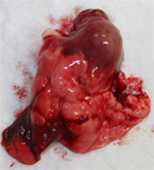

取り出した膀胱の腫瘍です。

膀胱および前立腺も切除しました。

術後は包皮から排尿できるようになりました。膀胱の腫瘍は平滑筋肉腫と言われる膀胱の腫瘍の種類にしては珍しい腫瘍でしたが、完全に取りきれているとのことでした。現在術後1年以上経ちますが経過良好で過ごしています。